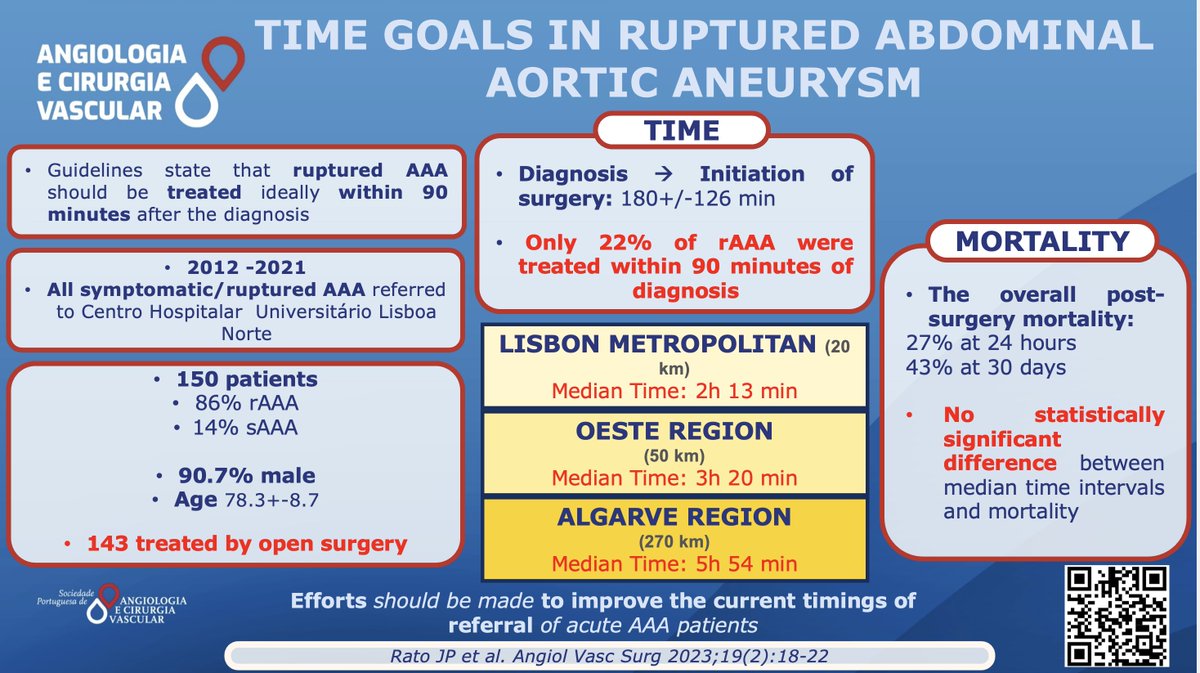

Do you comply with the average time recommended by the guidelines in the treatment of ruptured AAA? Read more about Rato JP et al experience here: acvjournal.com/index.php/acv/… #spacv #rupturedAAA #vascularsurgery Ryan Gouveia e Melo ESVS Society for Vascular Surgery Vascular News